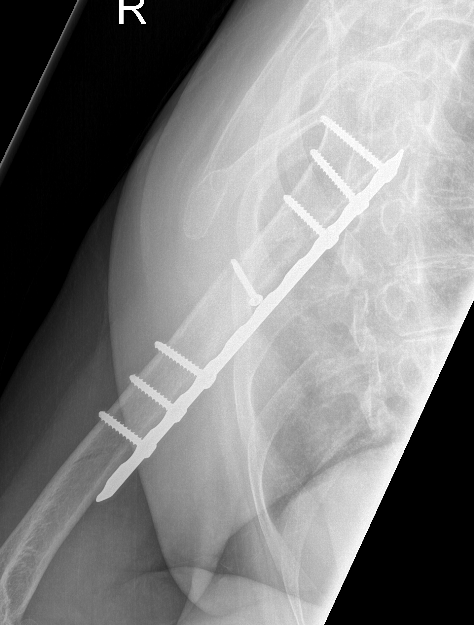

Prox humerus 1Prox humerus 2Prox humerus ORIFProximal humerus ORIF

Proximal third humerus ORIF of nonunion